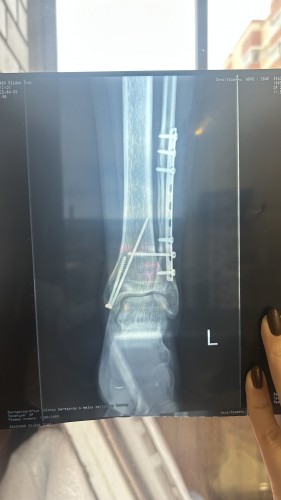

Shado26 писал(а):Здравствуйте! Весной дали категорию Г и отсрочку пол года, сегодня приходу в военкомат и говорят что я подхожу под категорию Б3 (у меня был перлом малой берцовой кости и большой берцовой кости со смещением лодыжки, на одной пластина на другой спица) я так понял меня хотят забрать в армию где у меня не будет нагрузки на ногу) в декабре мне уже 30 лет будет, если я сейчас по быстрому удалю пластину и спицу мне дадут отсрочку до конца декабря ? И вообще могут ли они меня забрать сейчас?